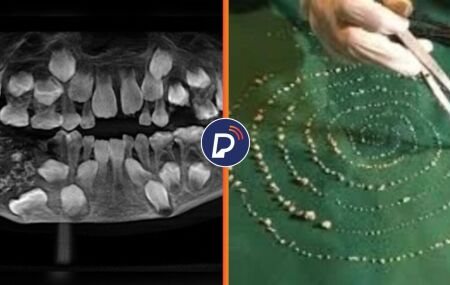

Ultrassom da boca do garoto e os dentes retirados.

Caso raro: criança de 7 anos tem 526 dentes retirados durante cirurgia

O ocorrido chamado de odontoma composto chamou a atenção dos médicos e acabou marcando a história da odontologia.